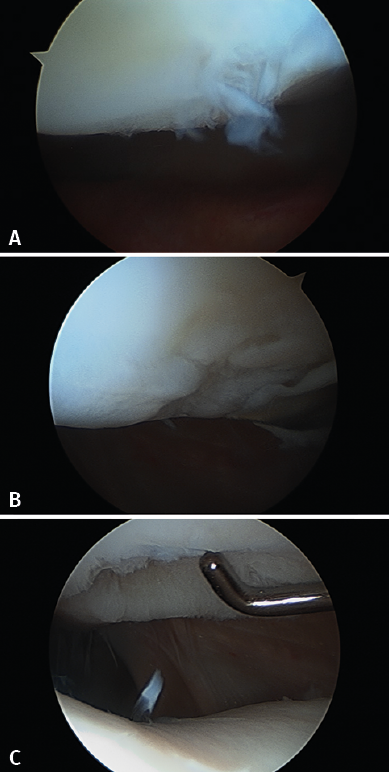

Figure 18. Photograph and arthroscopic view of an example of chondral lesion in the femoral condyle due to osteochondritis dissecans.

The results obtained with the first 50 patients subjected to treatment of the knee with ICC and involving two years of follow-up have recently been published(32). The studied patients presented a median age of 35 years (range: 18-49 years). Of these, 70% were males, and in 54% of the cases the chondral defect was located in the right knee. Most of them (72%) had undergone a previous surgery. In 66% of the cases the defect was of a chondral nature, in 20% the lesion was osteochondral, and in 14% the diagnosis was OCD (Figure 18). In the patients with previous surgery, the latter was carried out due to cartilage problems in 22 cases - the most frequent condition being microfractures (in 50% of the cases with previous cartilage surgeries).